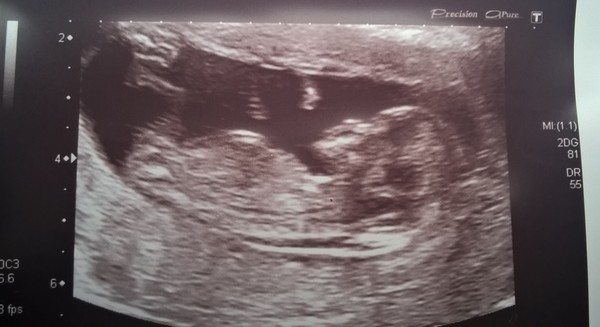

Scan day today for me, all good and very wriggly baby. Poorly toddler though which is less good!

Lovely pic, Bish. Hope your little boy is better soon.

Lovely scan bish Smile I'm really missing my fortnightly scans I was having! Counting down to out 16 wk private scan it can't come soon enough!

Lovely scan Bish! I sent you a PM on Facebook, so hopefully sent it to the right account!

Lovely scan bish

LOVELY scan picture Bish! Don't think I'll ever grow tired of seeing scan pictures now. Used to wonder what all the fuss was about before I had my own but now I'm obsessed with them!